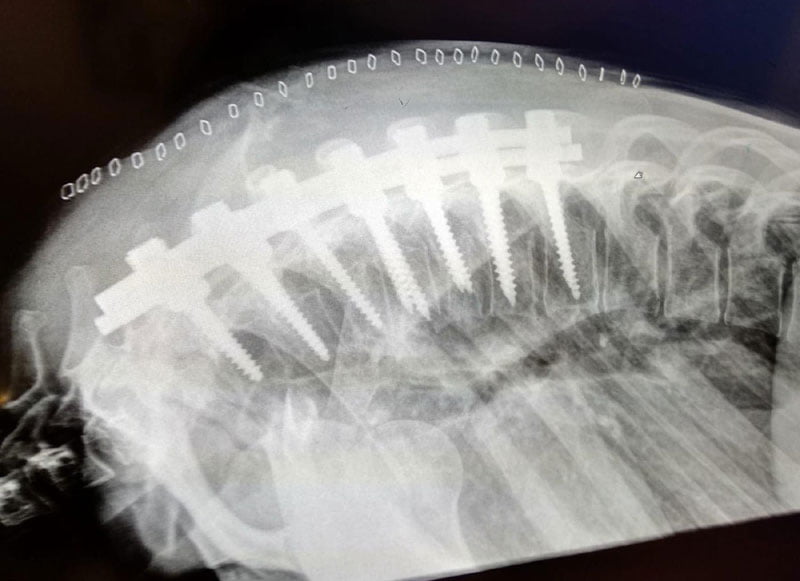

Celle qui a été la première fille à marquer des points dans le CEV 125cc avant d’être la coéquipière en Grands Prix d’un certain Maverick Viñales en 2013 l’avoue elle-même, elle a hésité à publier les photos des radios de son dos après l’opération chirurgicale aux vertèbres D4 et D6 faisant suite à une grave chute lors d’un test privé à Estoril au Portugal, au guidon de sa Kawasaki Ninja 400 du team Provec : Effroyable !